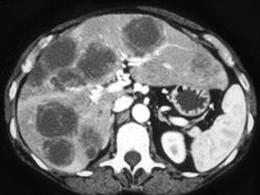

问题 男,54岁,患者一年前行结肠癌手术,癌胚抗原增高,影像检查如图,最可能的诊断是 ( )

选项 A、多发性肝囊肿 B、肝淋巴瘤 C、结肠癌肝转移 D、多发性肝脓肿 E、多发结节性肝癌

答案 C